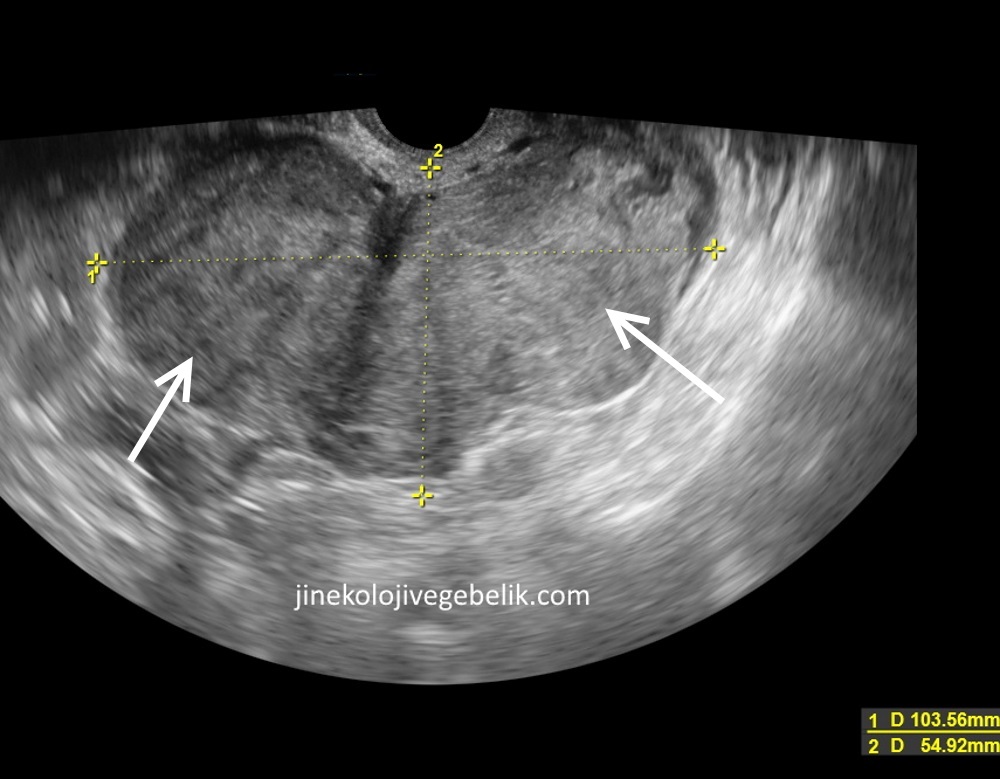

13 5 haftalik 3 aylik bebek ultrason goruntuleri aciklamali boyu ne ayr make it yourself